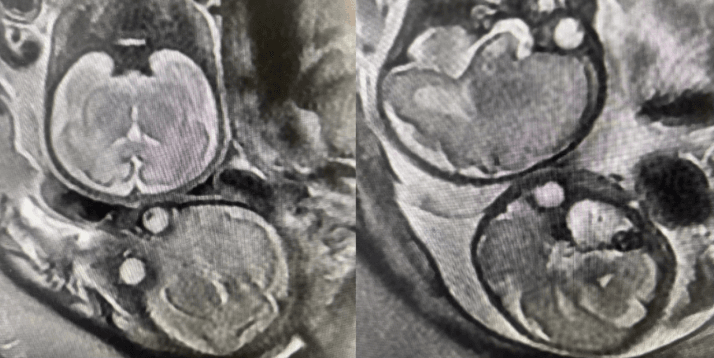

7月17日下午,宝鸡市妇幼保健院医学影像科成功为一名29+1周双胎妊娠孕妇完成了胎头核磁共振检查。此次检查不仅精准获取了胎儿颅脑影像,为临床诊疗提供了关键依据,也显示了该院在妇产科影像诊断领域的技术实力。

为保障检查的顺利与安全,医学影像科联合产科制定了个性化诊察方案,影像医生凭借丰富经验和精湛技术,耐心指导孕妇调整体位,密切监测体征状态,严格控制扫描参数,确保影像清晰准确。同时,考虑到孕妇的紧张情绪,医护人员全程给予心理安抚,有效缓解孕妇焦虑。最终,检查精准得出结果:胎儿1脐绕颈一周,胎儿2双侧侧脑室增宽。

高质量的影像数据清晰呈现了两个胎儿的颅脑形态、脑实质结构等关键信息,为临床医师评估胎儿发育状况、制定科学治疗方案提供了有力支撑。